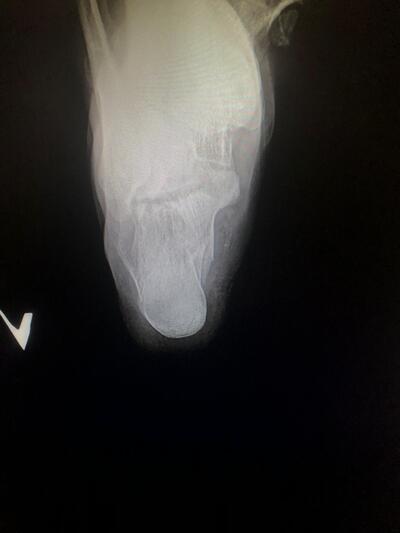

Рентген пятки полезная вещь. И еда для космонавтов нормальная по вкусу. Не такая чтоб каждый день есть, но вполне себе можно перекусить если что.

А насчет рентгена - нельзя же часто его делать, облучение и всё такое